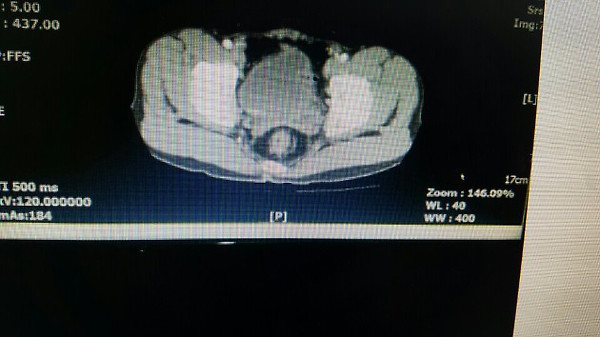

위사진은 암으로 추측되는부분이라도 개인병원 의사가 찾아주신 자료 중 하나입니다.

이게 맞을까요? 첫번째  2011년, 그다음 2015년 세번째도 2011년 그다음 2016년입니다. ....

CT 사진은 음양차이가 굉장히 중요하며 핸드폰으로 찍으신 사진으로는 판단하기가 힘드네요. 마지막 사진방광의 사진상왼쪽에 주변보다 하얗게 보이는 것이 암 소견입니다.

올려주신 영상은 PELVIS 쪽의 조영증강(ENHANCED) CT 검사네요.

첫째, 셋째 사진이 2011(초진검사) 하신 영상이고,

둘째 ,넷째 사진이 15,16년 사진이시죠.

사진이 명확치 않아 확인지 조금 어렵지만

사진상에 보이는 것은 네번째 마지막 사진에만 확실한 종양의심부분이 관찰이 되고 있습니다.

첫번째 사진 2011년 4월22일 ENHANCE CT 영상에서도

동그라미 쳐진 부분(화살표) 부분이 조영증강된 것이 확인이 됩니다.

나머지도 보시기 쉽게 동그라미 표시를 해드렸습니다.